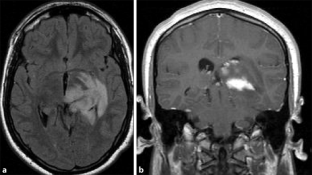

Abb. 3